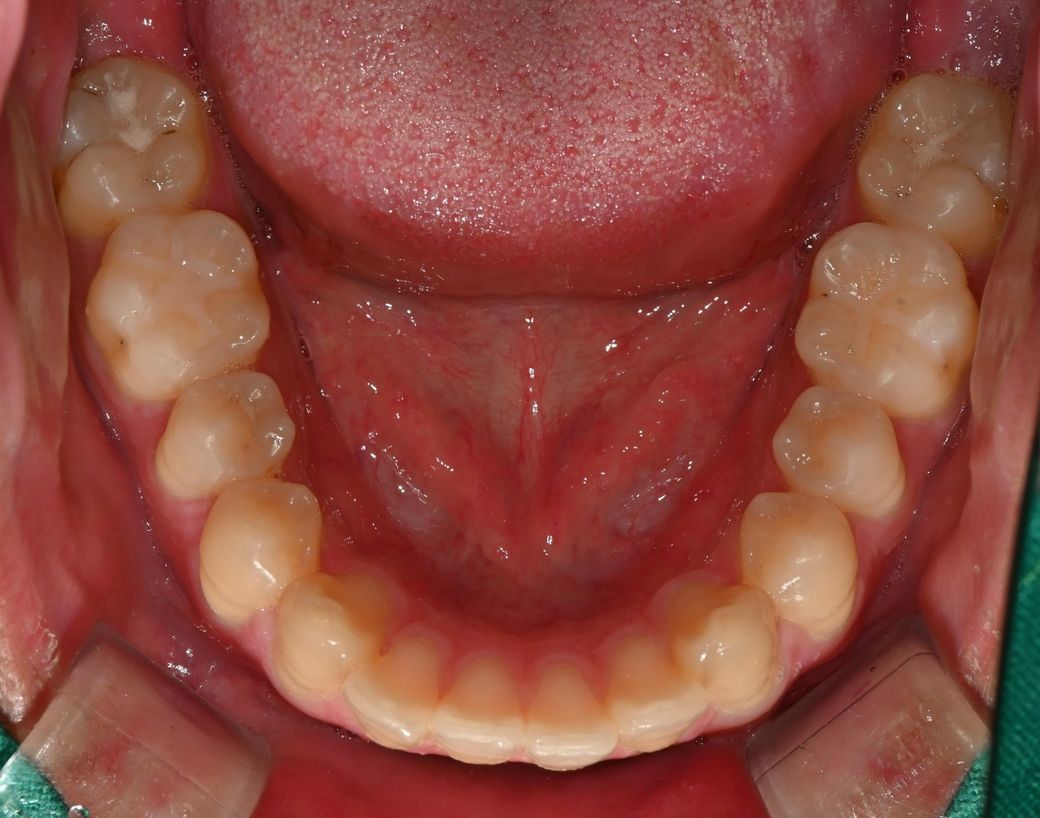

오늘 치과 2곳에서 원장님이 어금니 인레이가 필요한 충치가 있다고 하셨습니다. 위 사진에서 조금 긁어보시더니 C1 C2충치가 각각 있다는데, 어금니의경우 상아질에 접근한 충치의 범위가 커 보인다고 인레이를 하는게 좋겠다 하십니다. 특히 어금니는 씹는면 음영상 내부우식쪽으로 간거같다 하시는데 그정도로 제 충치상황이 악화된건가요? 파봐야 안다고하시든데 통증은 전혀 없지만 인레이 중 신경치료가능성이있나요?

• 2번 째 사진